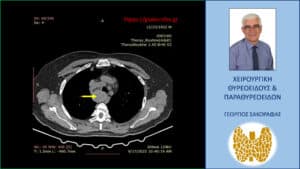

Αξονική τομογραφία – εγκάρσια διατομή σε χαμηλότερο επίπεδο, όπου φαίνεται η βαθιά κατάδυση του δεξιού λοβού στο μεσοθωράκιο